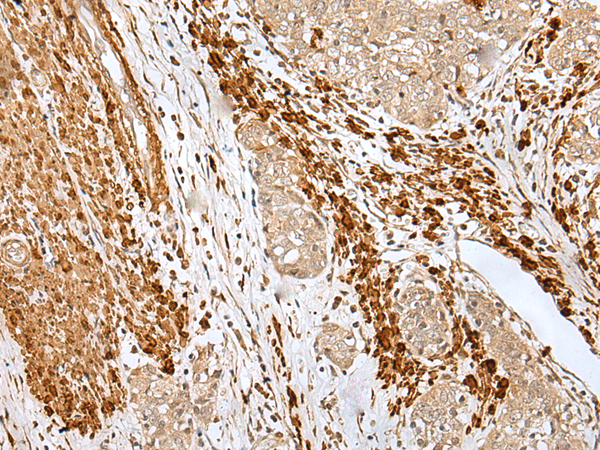

The image is immunohistochemistry of paraffin-embedded Human gastric cancer tissue using P12564(PF4 Antibody) at dilution 1/30. (Original magnification: ×200) |

The image is immunohistochemistry of paraffin-embedded Human esophagus cancer tissue using P12564(PF4 Antibody) at dilution 1/30. (Original magnification: ×200) |